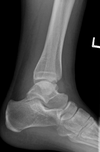

14

Q

error

A

external rotation

15

internal rotation